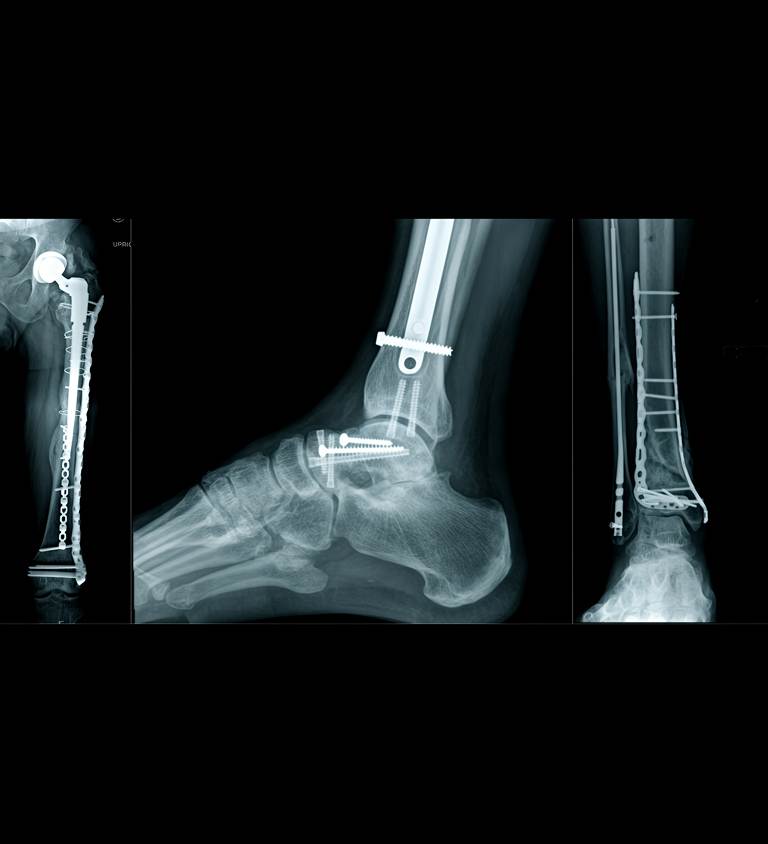

Multiple Fractures

Open Fractures

Dislocation with Fracture

This injury involves a joint being forced out of place, along with a nearby bone fracture. It commonly occurs in the shoulder or hip and requires precise realignment and stabilisation.

Crush Injuries

Polytrauma